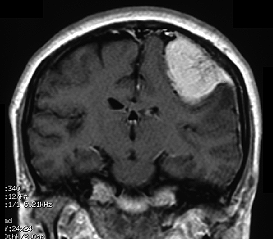

CT(コンピュータ断層撮影:X線を利用)やMRI(核磁気共鳴影像法:磁気を利用)による脳の断層画像でほとんど診断がつきます。しかし、他にも鑑別しなければならない病気があり最終的な確定診断は手術によって摘出した腫瘍を顕微鏡検査(病理検査)することでなされます。(図-2)

図-2